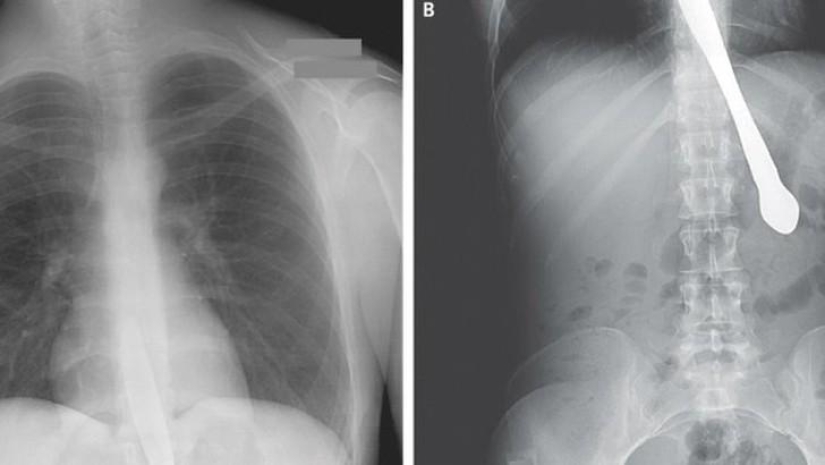

Bala.